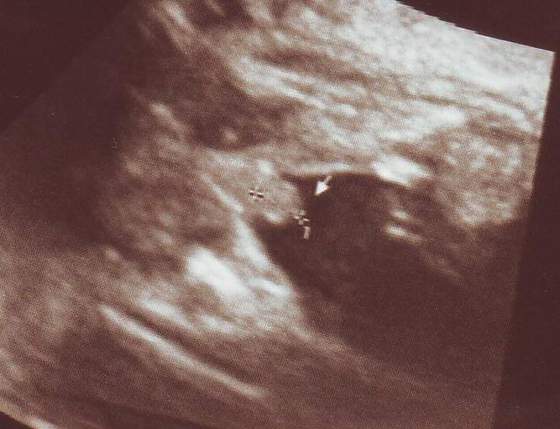

Moja córcia końcem 17 tygodnia:*